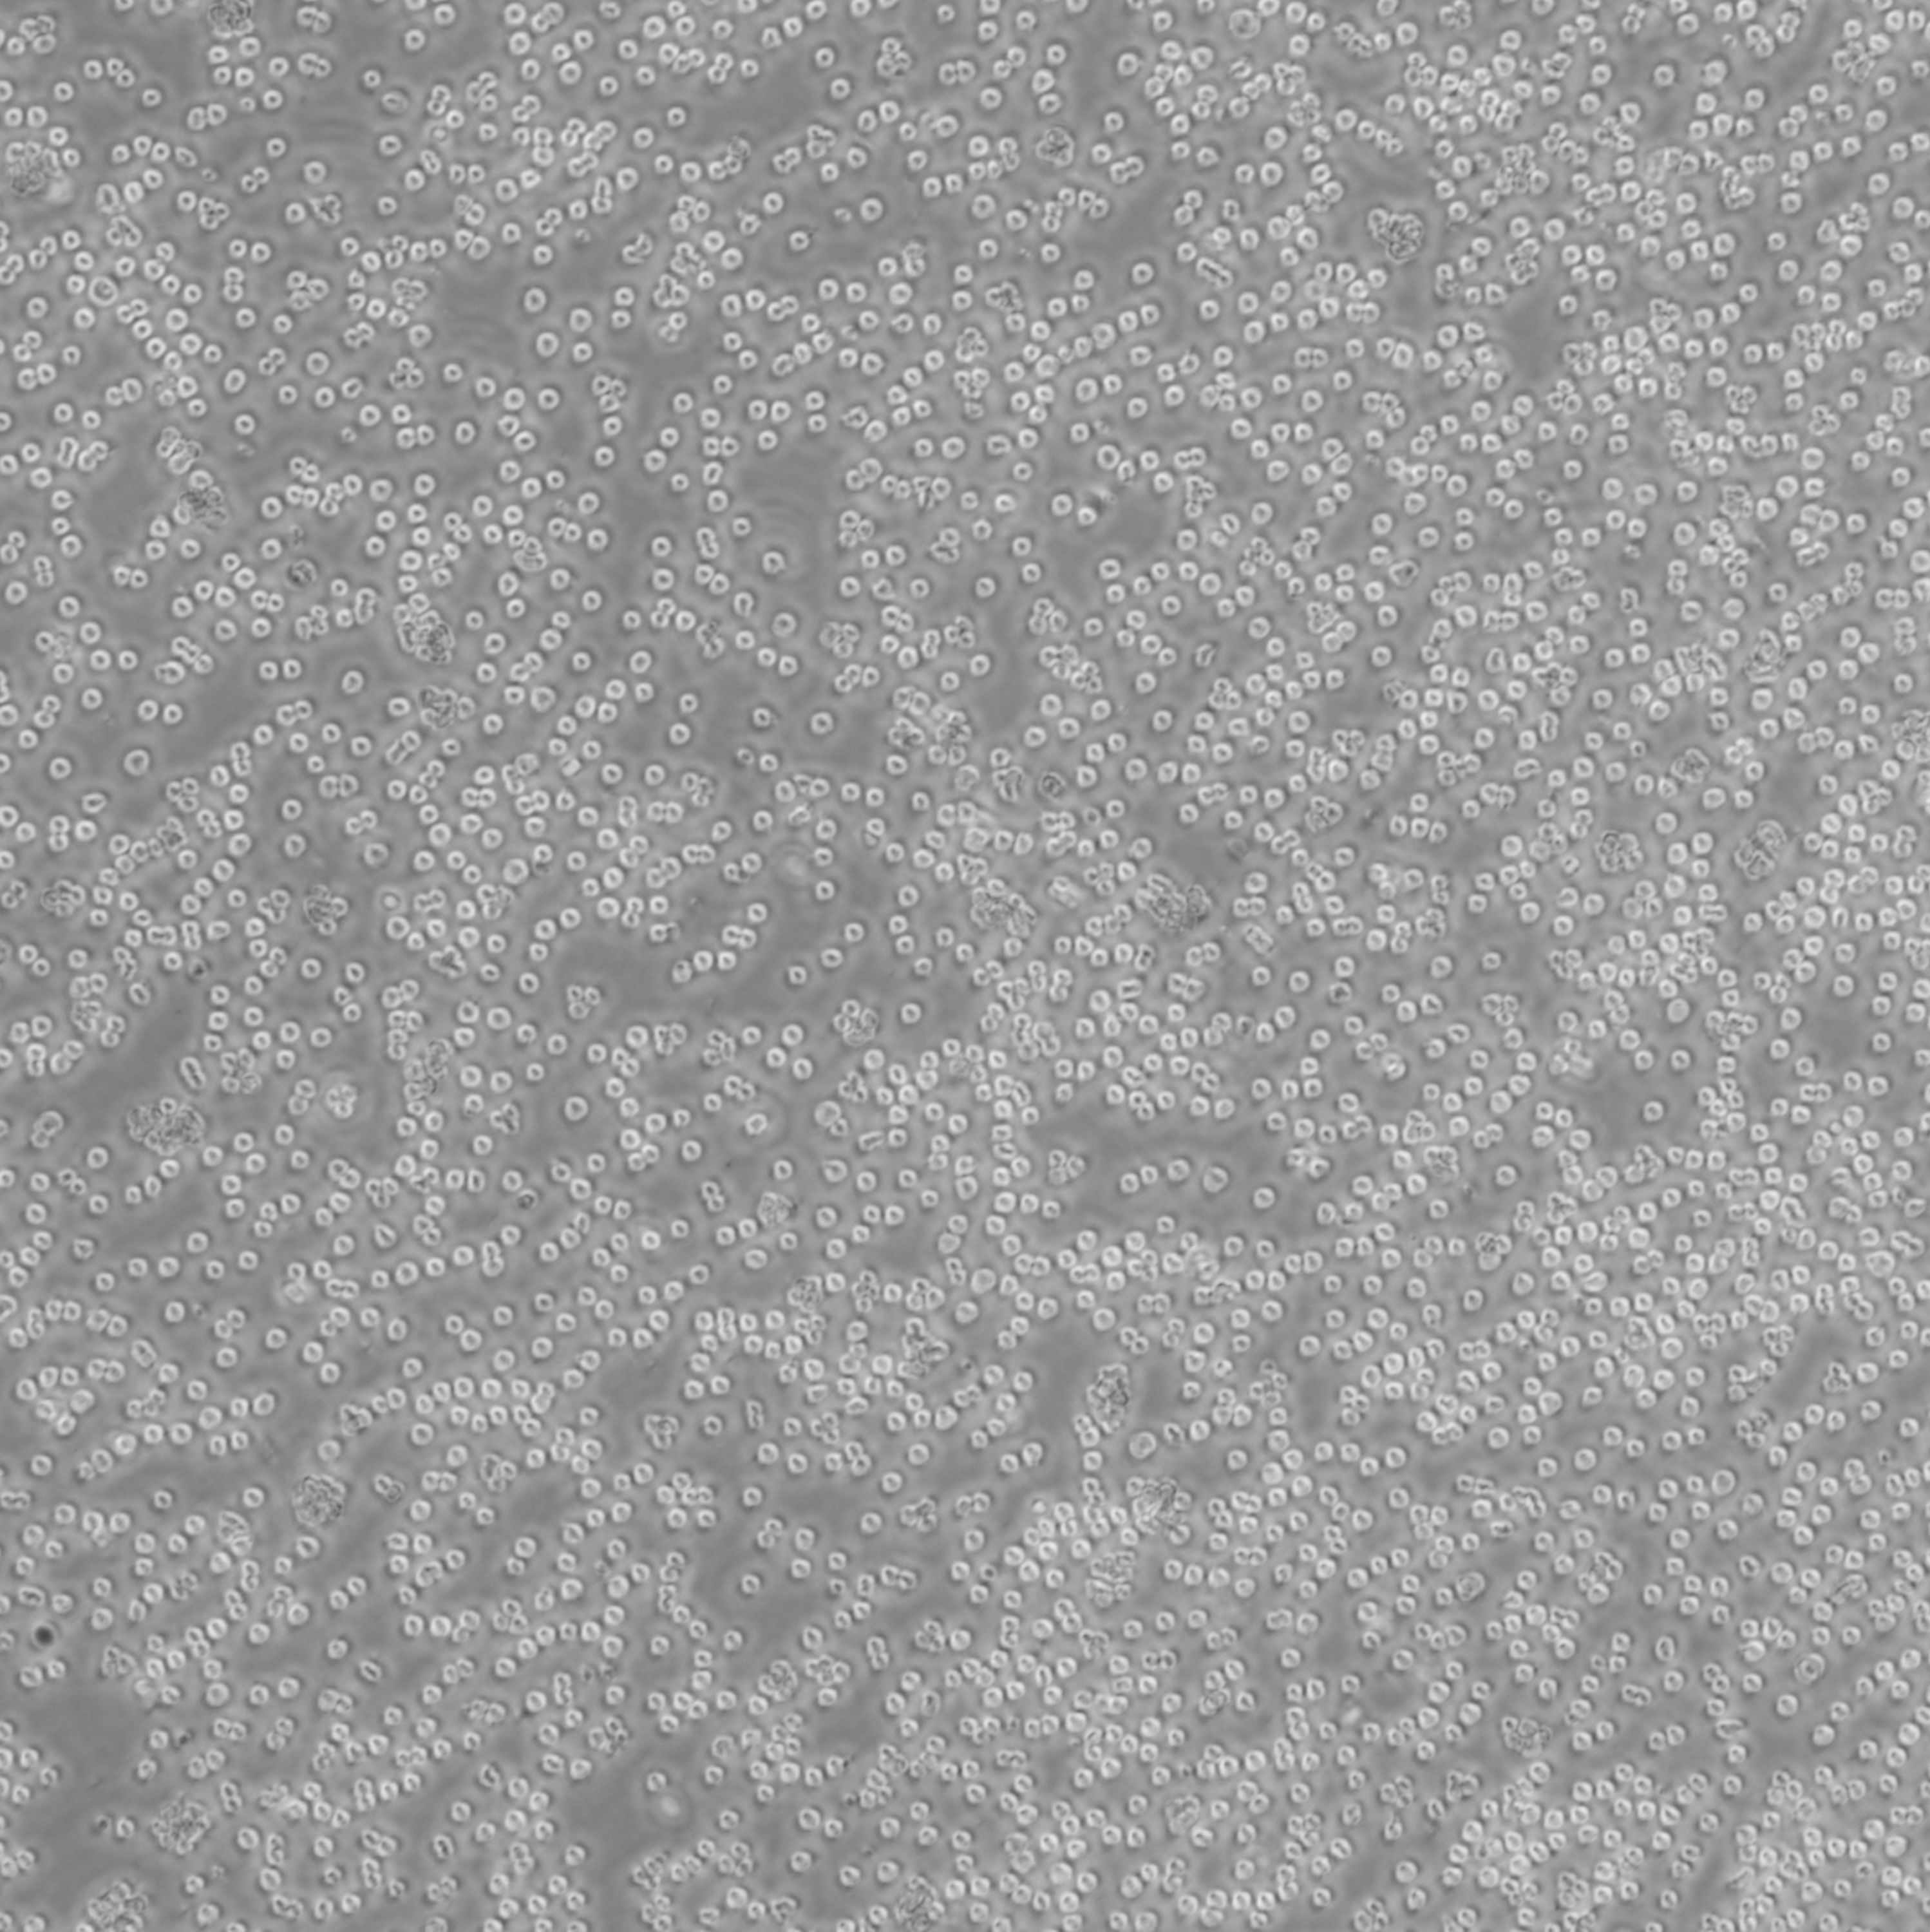

REC-1_人淋巴癌细胞

细胞名称: REC-1_人淋巴癌细胞

种属来源: 人

种属来源: 淋巴瘤

生长特性: 悬浮生长

细胞形态: 淋巴细胞样

培养条件: RPMI-1640 Medium+10% fetal bovine serum,37 ℃, 5% CO2

细胞规格: 1 X 106cells/T25或1 mL冻存管

传代方法:1:3传代, 2-3天传1代

冻存条件: 90% FBS + 10% DMSO